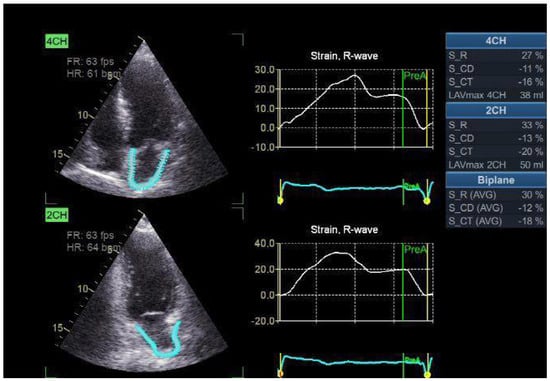

4. LA Longitudinal Strain Analysis

The two-dimensional strain analysis tool on the Echo PAC workstation (GE Healthcare) was used to measure LA strain and strain rate. The endocardial border outlines the whole myocardial area of interest (ROI) of the left atrium, much as it does for the left ventricle. With a default width of 3 mm, it is advised to use an adjustable ROI. The item’s size and location may be altered by the operator to meet the left atrial wall’s thickness without touching the pericardium. After dividing the atrial endocardium into six segments, the computer automatically rejected and removed parts that were not presented properly from the research. The software created the global longitudinal strain and strain rate profiles for each apical view. In order to accomplish appropriate tracking, the operator has the option of either retrying the imaging process or modifying the software settings, such as the smoothing algorithms and the ROI width. The electrocardiograph was recorded during three consecutive heartbeats, and the apical four-chamber and two-chamber images were acquired. The absolute strain value in the three LA phases—conduit strain in early diastole (LASct), reservoir strain in systole (LASr), and contraction strain in late diastole (LAScd)—is known as the LA strain. The first “0” reference point was the LV end-diastole. These strains are LASr, which is defined as the difference between the end-diastole and filling onset; LAScd, which is defined as the difference between the filling onset and the atrial contraction onset (prior to the Doppler A-wave onset); and LASct, which is defined as the difference between the filling onset and the atrial diastole end. The average of the relevant values from both views was used to estimate the global strain (Figure 2) [13].

Figure 2. LA two-dimensional strain. LASr is assessed as the difference between onset of filling and end-diastole; LAScd is assessed as the difference between atrial contraction and filling onset; LASct is assessed as the difference between atrial filling onset and end-diastole.